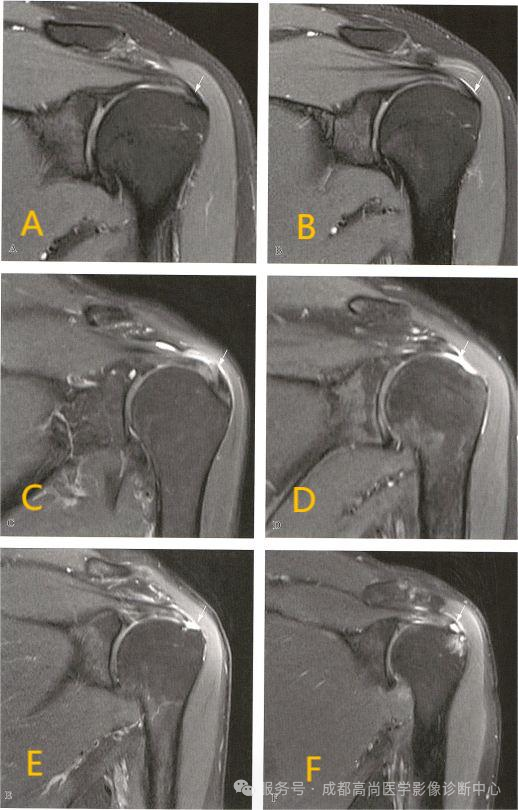

示例:

A. 正常冈上肌腱前部;B. 正常冈上肌腱中部层面;C. 冈上肌腱变性;D. 冈上肌腱中部完全撕裂;E. 冈上肌腱滑囊面部分撕裂;F. 冈上肌腱关节面部分撕裂

MRI 可帮助确定肌腱损伤的损伤部位和严重程度,尤其是 MRI 可以清晰的显示肩袖的部分撕裂, 对诊断具有较高的价值。